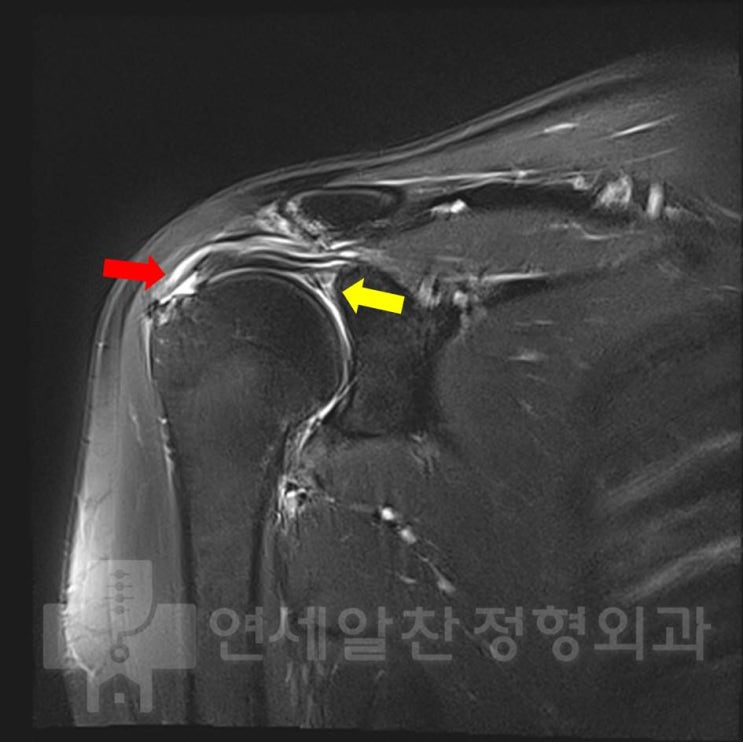

Arthroscopic Double-Row Suture Bridge Repair for Rotator Cuff Tear (Supraspinatus Tear)

#rotator cuff tear#supraspinatus tear#double-row suture bridge#arthroscopic repair